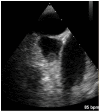

Atrial fibrillation (AF) can cause thrombi formation and subsequent emboli deposition in systemic arteries, leading to various organ ischemia and infarction. Anticoagulation therapy can reduce the risk of thrombus formation and embolization, and is initiated based on a patient's risk score, which is frequently estimated with the CHA2DS2-VASc score. We present a case of thromboembolism (TE) where a low CHA2DS2-VASc score suggested a low-moderate risk of systemic embolization, but an elevated plasma D-dimer value prompted further investigation which revealed an intracardiac thrombus with renal embolism. The patient is a 63-year-old male with past medical history of hypertension and AF treated with ablation 2 years prior presenting with sharp right flank pain of 5-hour duration. Primary workup and imaging were unrevealing at the time, and a low CHA2DS2-VASc score was suggestive of aspirin therapy. However, an elevated D-dimer of 289 ng/mL and a transient increase in creatinine pointed to possible etiology of embolic origin. The diagnosis was confirmed with computed tomography (CT) with contrast and transesophageal echocardiogram, revealing renal infarcts and the source of the emboli, respectively. The patient was treated with heparin and transitioned to apixaban prior to discharge with full resolution of symptoms. Through this case, we wish to show D-dimer's predictive value of TE, as well as its potential benefit in risk assessment in patients with AF.